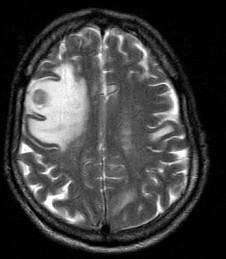

问题 男,77岁,胃癌术后2年,头痛1月,请结合影像图像选择最可能的诊断()

选项 A.脑脓肿 B.松果体瘤 C.神经胶质瘤 D.胃癌脑转移 E.脑膜炎

答案 D